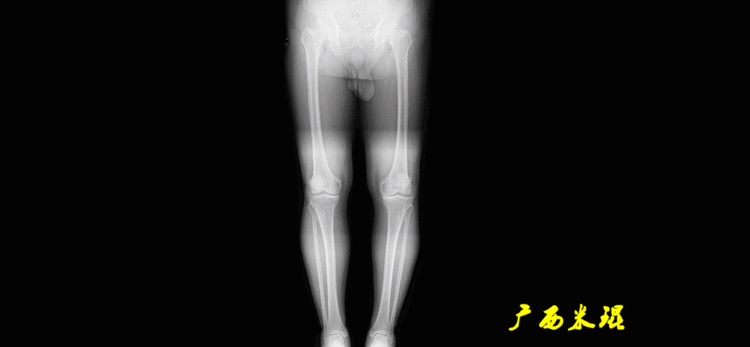

下肢力线及相关角度测量的前提是必须拍摄标准的站立位也就是负重位的下肢全长片。目前这样的照片都是放射科的技师在电脑上拼接出来的,大部分医院的DR都能够做到这一点。

患者直立于摄影架上,后背贴近摄影架,双手自然下垂,膝关节尽量伸直,足部与双肩同宽,要求投照时双髌骨朝正前方,通常患者双足尖应平行向前即可。

提醒一下大家,拍摄过程中应避免下肢的外旋和内旋。如果有一侧肢体短缩时,投照应当用脚垫垫高短缩肢体,使骨盆保持水平,这样下肢短缩测量才精确。如果有肢体旋转畸形时,还是以髌骨朝前为标准,虽然此时双足可能不能保持平行。

无论如何,拍摄出来的下肢全长片必须包含髋关节中心、膝关节中心及踝关节中心,否则对临床是无用的。有了一张下肢的全长照片,我们需要确定下肢关节的中心点,通过中心点画出下肢的各种轴线,然后利用轴线与关节线的相交得出各种所需要的角度。

2、画出下肢的轴线确定髋关节、膝关节、踝关节的中心点后,我们才能了解下肢的几个轴线。(1)解剖轴股骨和胫骨的骨干中线为解剖轴,股骨解剖轴和胫骨解剖轴的夹角正常值为174°±1°。

机械轴要分前后位及侧位,站立前后位(也就是冠状面)股骨头中心与踝关节中心的连线通过膝关节中心,这是下肢的机械轴线,也就是下肢力线,常说Mikulicz线。冠状面的力线评估在临床工作中最常用、最基础、最重要。